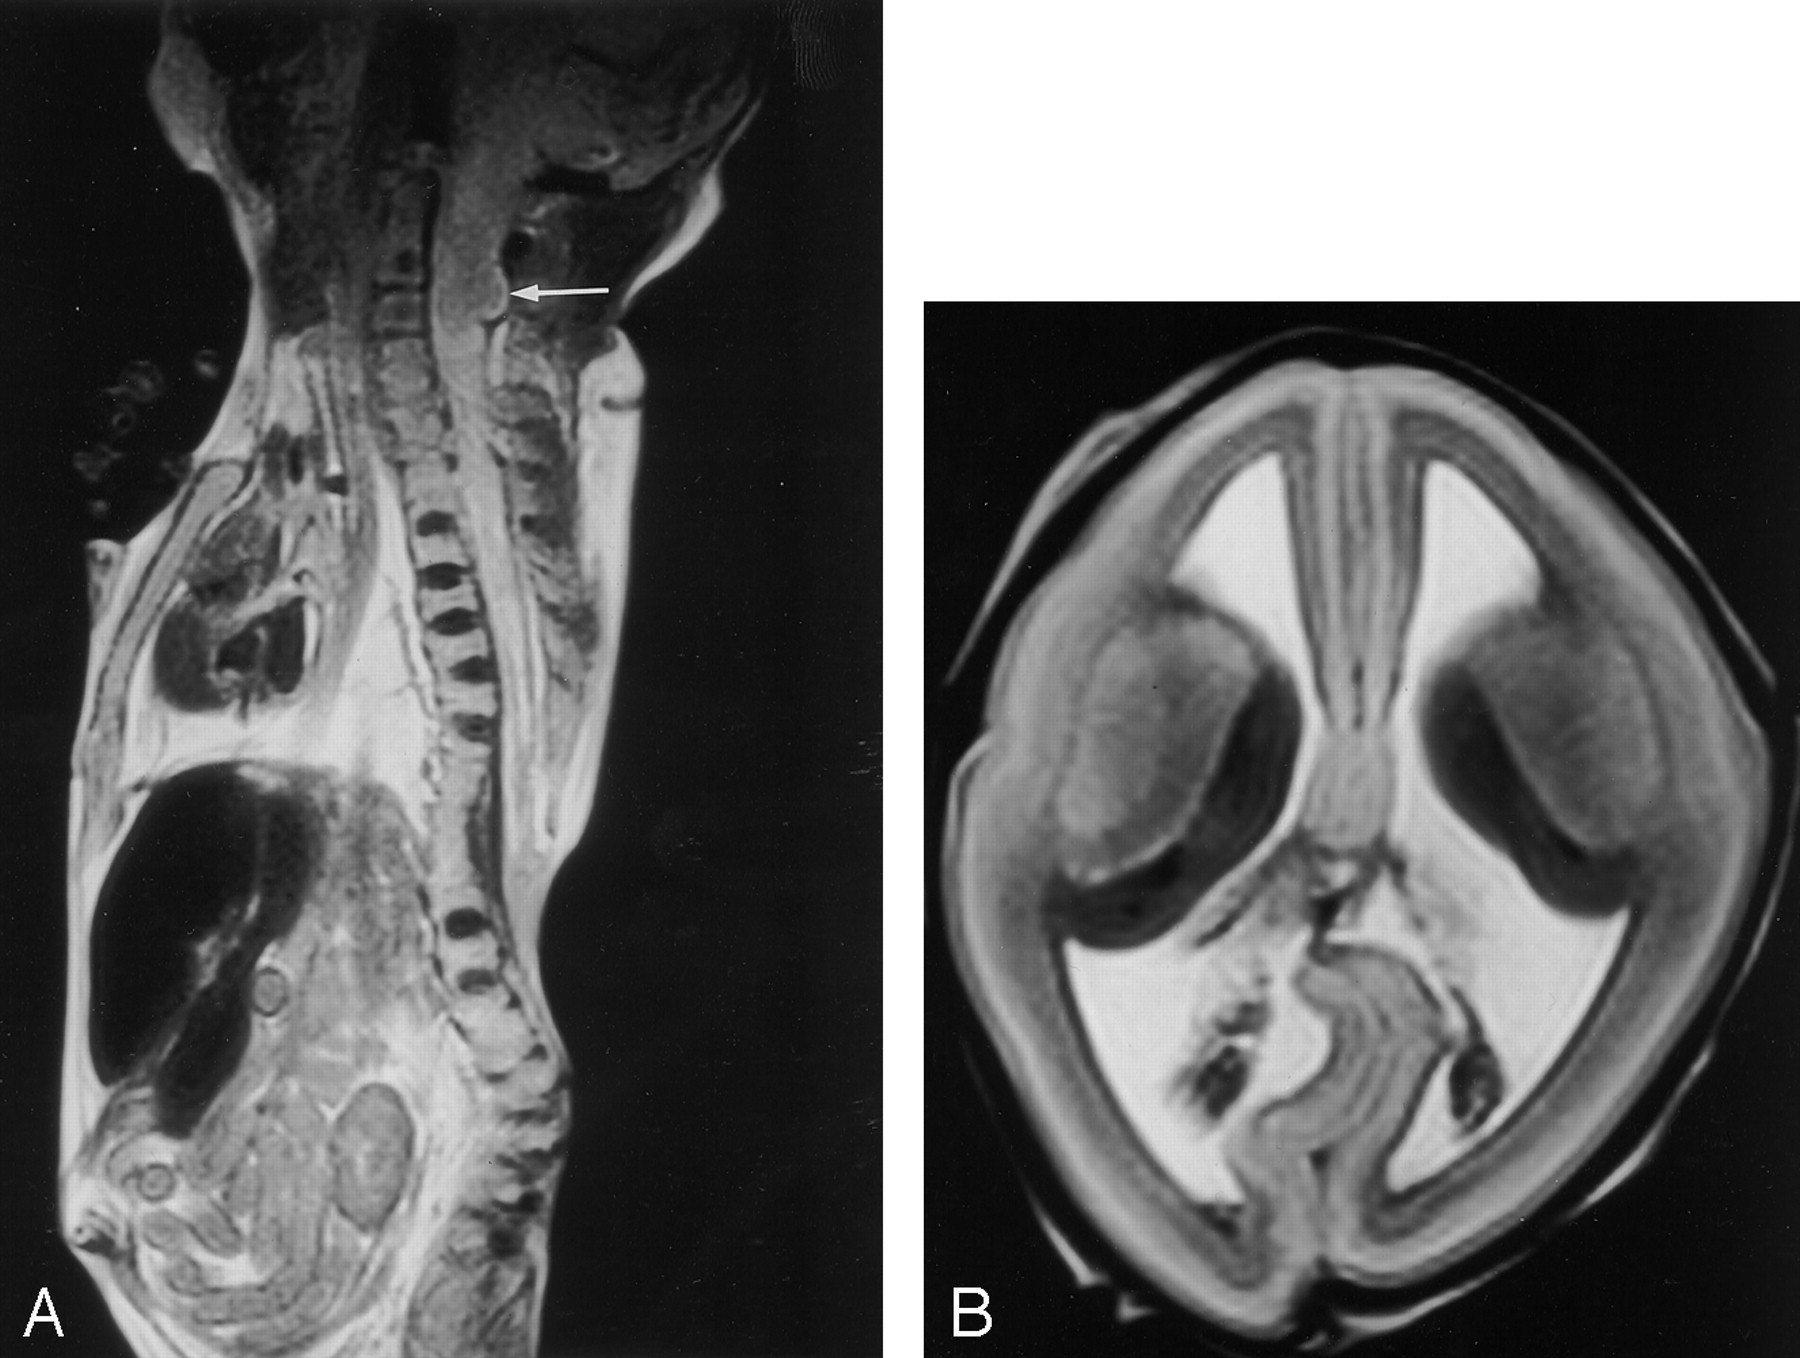

A, Sagittal spine and B, axial brain MR images in a 20-week fetus after a therapeutic abortion because of a sonographic diagnosis of myelomeningocele and Chiari II malformation. These findings were confirmed with postmortem MR imaging and autopsy. The spine MR image (A) shows a low thoracic myelomeningocele with an adjacent complicated fusion defect of the lower thoracic-upper lumbar vertebral bodies. There is also extensive syringohydromyelia. The cerebellar tonsils (arrow) are abnormally low (at C3), indicating a Chiari II abnormality, and images of the brain (not shown) confirmed the presence of a small posterior fossa. This brain MR image (B) shows ventriculomegaly and the “lemon-shaped” deformity recognized on sonograms in cases such as these.